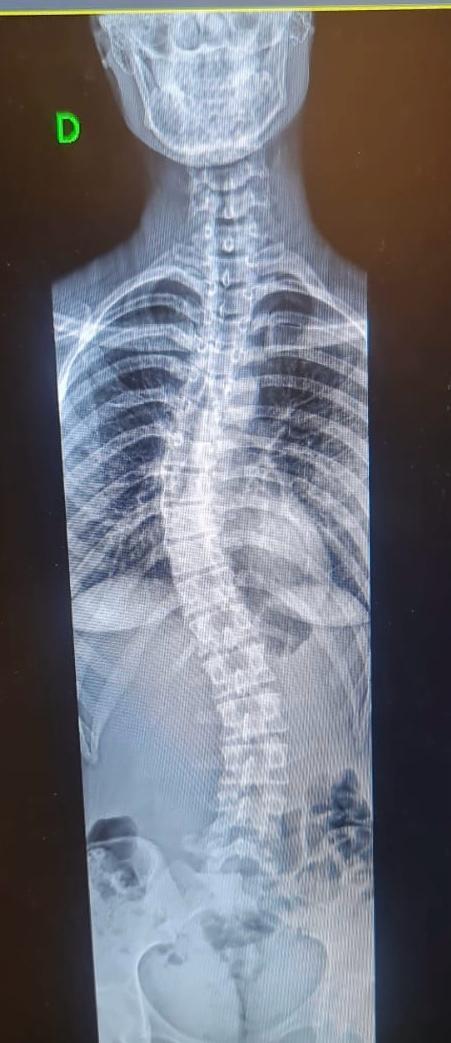

O Hospital Ortopédico do Estado da Bahia (HOE) oferece, de forma inédita aos pacientes do SUS no estado, o exame de escanometria. O procedimento, uma espécie de raio-x digitalizado, antes disponível na Bahia apenas na rede privada de saúde, realiza medidas do corpo e dos membros do paciente, permitindo avaliar, com precisão, o crescimento e o desenvolvimento dos ossos, assim como os desvios da coluna vertebral, que acometem faixas específicas da população.

A escanometria ajuda a identificar diversos problemas com antecedência. Entre eles, deformidades e lesões traumáticas, além de contribuir na preparação e acompanhamento de tratamentos cirúrgicos e clínicos envolvendo ossos e articulações.

O exame é ideal para verificar alterações estruturais nos membros, coluna e até no alinhamento das pernas e dos braços. O procedimento passou a fazer parte do moderno centro de bioimagem do hospital, ampliando sua capacidade de atendimento. Na unidade, já foram realizadas 329 escanometria, nas quais foram possíveis observar, de forma detalhada, toda a estrutura óssea dos pacientes, por meio de sensores extremamente precisos, facilitando e acelerando o diagnóstico médico.